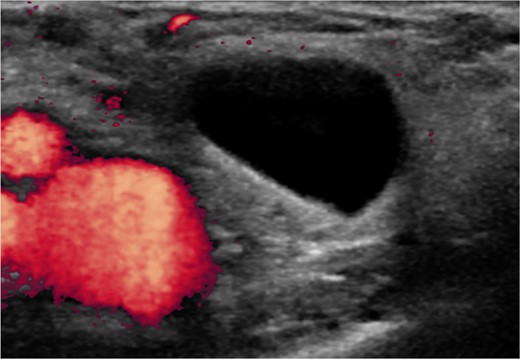

Our patient is a 35-year-old female who presented with a painful, tender right groin lump for a 6-week duration. An ultrasound revealed a thin-walled fluid collection medial to the femoral vessels (Fig. 1). She was diagnosed with a femoral hernia and offered a repair of the hernia. Due to an improvement in symptoms since onset and clinic visit and in anticipation of the upcoming summer, she opted for elective repair. Unfortunately, her symptoms worsened prior to her surgery date resulting in an expedited operation. The patient was taken to the operating room for repair of her hernia. An incision was made overlying her groin bulge. She was found to have an obvious hernia sac below the inguinal ligament which was dissected from the femoral vessels and pubic tubercle. Due to the small size of the defect, <1 cm, the sac and contents were unable to be reduced into the abdomen. The decision was made to ligate the sac at the level of the defect. After ligation and upon examination, the distal tip of the appendix was found to be within the hernia sac and transected. The decision was made to extend the skin incision laterally in anticipation of accessing the peritoneal cavity. The external oblique, internal oblique and transversalis layers were incised in the direction of their respective fibers. The cecum was identified and brought out of the incision. A window was made at the base of the appendix which was ligated and the completion appendectomy performed. The mesoappendix was then separately ligated. The cecum was returned to the abdomen and the three muscle layers were closed individually. Due to a small amount of spillage, the decision was made to perform a primary repair of the femoral defect. Prolene suture was used to perform the herniorrhaphy, approximating the inferior portion of the inguinal ligament to cooper’s ligament inferiorly. The patient tolerated the procedure well and was discharged to home the same day. The final pathology confirmed acute appendicitis. The patient reported mild abdominal bloating at her 2-week postoperative visit that resolved by her 4-week postoperative visit.

A thin-walled fluid filled sac medial to the femoral vessels diagnostic of a femoral hernia.